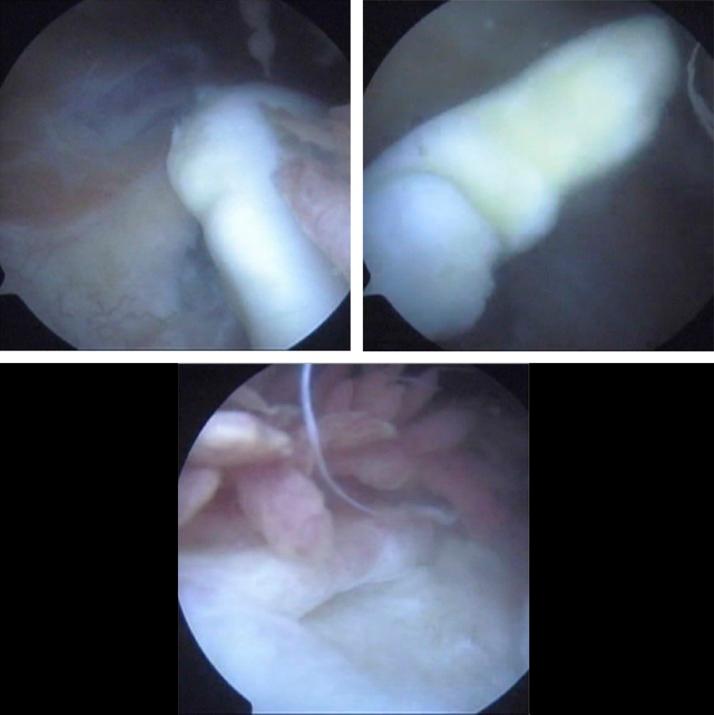

The authors report a case of a late repair of a missed, large, osteochondral fracture of the femoral trochlea in a 14-year-old boy due to lateral patellar dislocation after a twisting injury of the knee a year ago. The late-1 year after the knee injury-imaging assessment of the patient regarding radiograph images, CT scan, and MRI was misleading, misinterpreted, and failed to reveal this osteochondral fracture. The free osteochondral fragment was detected during diagnostic arthroscopy. Open reduction and fixation of the osteochondral fragment with bioabsorbable pins were done, and healing was achieved within an acceptable time. The patient's clinical and imaging examination with knee MRI, a year after the surgical treatment, was highly satisfactory. Fixation with bioabsorbable pins showed to be a worthwhile option in this case. The technique used was straightforward, with excellent short- and long-term results. Bioabsorbable pins may be used to restore successfully even an old, large osteochondral fracture in the immature skeleton.

作者报告了一例14岁男孩的病例,该男孩在一年前膝关节扭伤后因髌骨外侧脱位导致股骨滑车一处漏诊的大型骨软骨骨折延迟修复。膝关节损伤1年后对患者进行的影像学评估,包括X线片、CT扫描和MRI,结果具有误导性,解读错误,未能发现该骨软骨骨折。在诊断性关节镜检查期间发现了游离的骨软骨碎片。采用生物可吸收针进行了骨软骨碎片的切开复位内固定,骨折在可接受的时间内愈合。手术治疗一年后,对患者进行的膝关节MRI临床和影像学检查结果非常令人满意。在这种情况下,使用生物可吸收针固定是一种值得选择的方法。所采用的技术简单直接,短期和长期效果都很好。生物可吸收针甚至可以成功修复未成熟骨骼中的陈旧性大型骨软骨骨折。